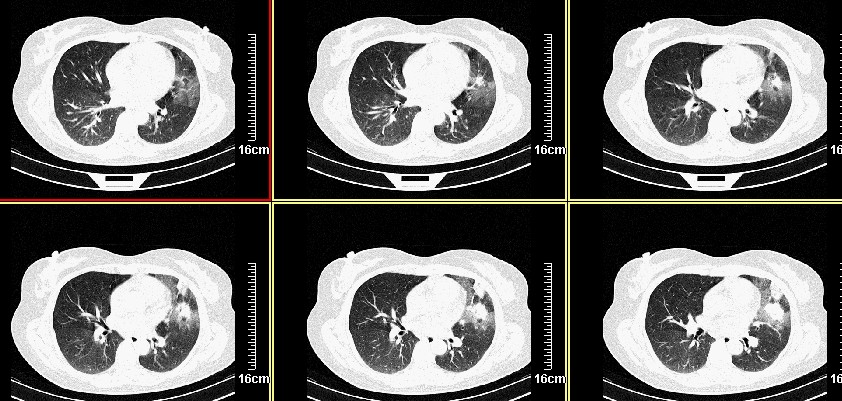

一周之后 复查结果 5mm扫描 40多岁 我们医院的护士

病史?1.首先考虑左肺上叶占位(ca可能);

2.继发型肺tb?

3.单纯感染不除外。

左上肺周围型肺癌可能性大,楼主片子太小

考虑左肺上叶周围型肺癌可能性大.

首先考虑左上肺周围型肺癌可能性大,但肺内炎症(肺脓肿形成前期)有待排除

第八幅图像,典型毛刺,像日本鬼子的膏药军旗一样,一看就不是个好东西

左肺上叶肿块,肺窗周围有“晕征”,纵隔窗有毛刺,临床资料???只能考虑占位???